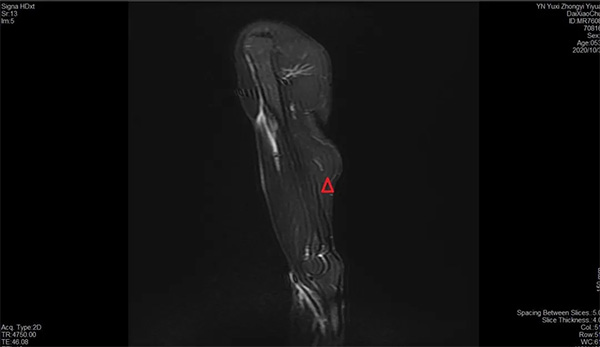

近日,一名53歲的壯漢因?yàn)樘嶂匚锢瓊笊媳?,?dǎo)致左肩及左上臂疼痛,同時在屈肘時在上臂出現(xiàn)形似“大力水手”的腫塊,受傷后到我院骨傷二科(關(guān)節(jié)與運(yùn)動醫(yī)學(xué)科)門診就診,予行左肩及左上臂核磁共振檢查結(jié)果顯示:左肱二頭肌長頭肌腱斷裂,這就是我們?nèi)粘I钪鞋F(xiàn)實(shí)版的大力水手征,由于肌腱的斷裂導(dǎo)致這名壯漢左上臂一定力量的減弱。

肱二頭肌攣縮征象

肱二頭肌斷裂征象